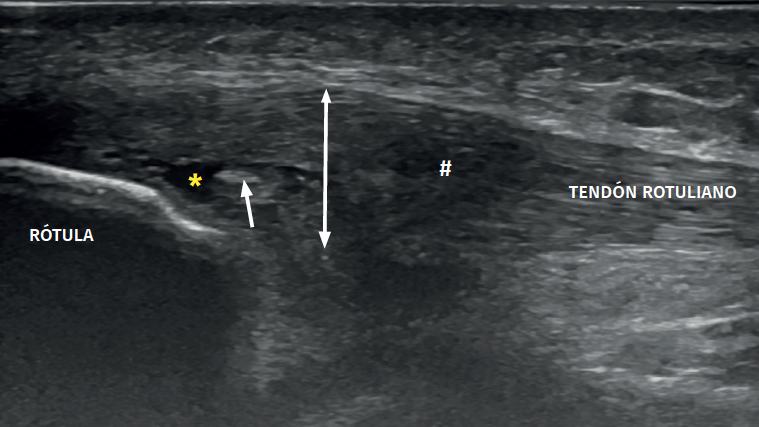

Figure 3. Ultrasound view of proximal patellar tendinopathy with linear probe in craniocaudal longitudinal panoramic view (from left to right). Note the area of decreased echogenicity (hypoechoic), marked with an asterisk, loss of the fibrillar pattern in the deepest and proximal region of the tendon secondary to disruption of the collagen bands, and anteroposterior 8.5 mm thickening (double arrow). ATT: anterior tibial tuberosity.

The ultrasound study of a damaged tendon evidences hypoechogenicity and loss of the fibrillar pattern, the appearance of disorganised connective tissue, and thickening of the tendon (Figure 3). In some cases we observe well delimited hypoechoic images indicating intra-substance rupture with nodular or fibrillar shapes, commonly manifesting in the deepest zone of the tendon in the lower pole adjacent to the patella (Figure 4).

Figure 4. High-resolution ultrasound study of patellar tendinopathy. Linear probe with longitudinal view. The double arrow shows increased tendon thickness, with hypoechogenic altered fibrillar pattern (#), intra-substance rupture (asterisk) and fibrosis (arrow).

In the middle portion of the tendon we may observe thickening (> 3.5 mm) associated to hypoechoic areas with zones of disorganised collagen and loss of the fibrillar pattern.

It is also common to identify cortical irregularities in the proximal enthesis of the tendon at the point where it joins the patella, involvement of the paratendon and adherences to Hoffa's fat pad. Any calcifications will be seen as white hyperechogenic zones (Figure 5).